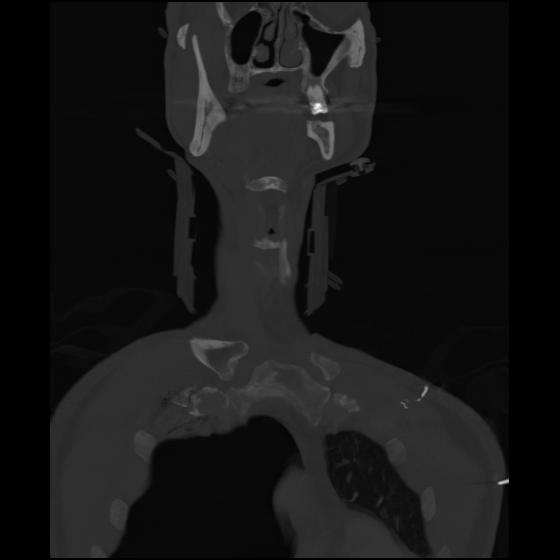

23 ANGIO,CE,Cor-MIP,5.000,ANGIO,Cor-MIP,